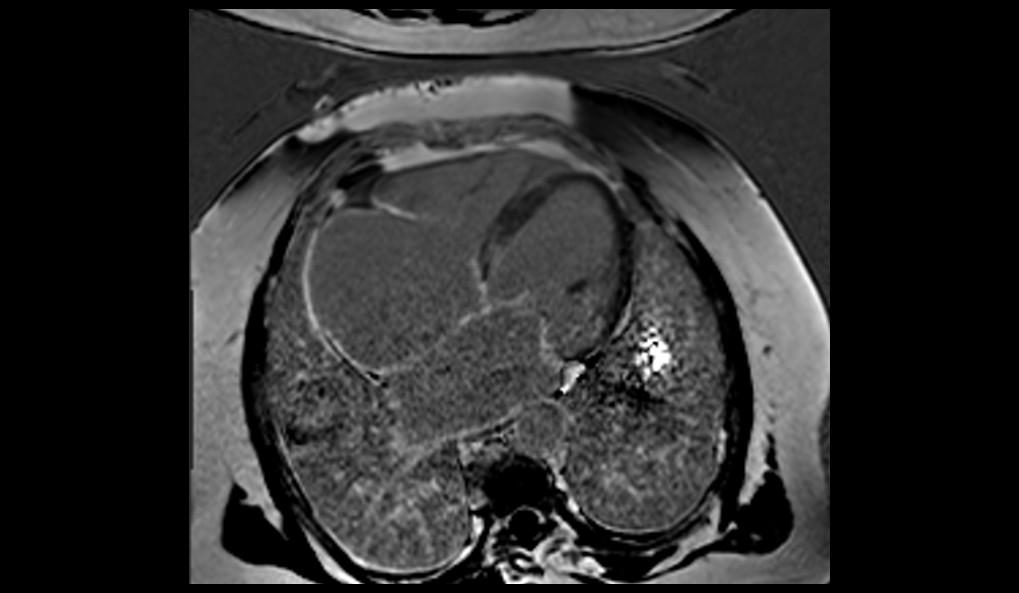

El examen de RMC se realizó en el equipo MAGNETOM Altea 1.5T. Se realizaron secuencias de CINE PSIF, FSE black-blood T1 y T2, phase-contrast, mapeo miocárdico (MyoMaps) T1/T2/T2* y LGE TRUFI high-resolution después de la inyección de contraste (DOTA-Gd 0,5M 0,2mmol/kg).

La RMC evidenció dilatación biatrial importante (AD=170ml/m2 y AE=120ml/m2), dilatación biventricular discreta (VDFVD=115ml/m2 y VDFVE=103ml/m2), FEVD 49%, FEVI 45%, rectificación del septo interventricular, insuficiencia tricúspide moderada, derrame pericárdico discreto, realce tardío heterogéneo en VI de patrones mesocárdico y subendocárdico en segmentos anteriores, anteroseptales, inferoseptales, inferiores y anterolaterales con distribución predominante medio-basal y realce tardío biatrial estadio UTAH IV. El MyoMaps en septo interventricular reveló elevaciones de tiempos T1 nativo (1070ms), T2 (58ms) y del volumen extracelular (33%) con T2* normal (28ms).

Los hallazgos de la RMC son compatibles con el diagnóstico de amiloidosis cardíaca. El patrón de cardiomiopatía dilatada con realce tardío (fibrosis) multisegmentar en VI, evitando segmentos apicales, elevaciones de T1 y VEC y fibrosis biatrial son hallazgos típicos de amiloidosis, especialmente en el subtipo ATTR. La Resonancia Magnética del Corazón, a través de su evaluación multiparamétrica, permite una diferenciación etiológica precisa de las cardiomiopatías, siendo indicada por las mejores guías como examen diagnóstico de primera línea en la investigación de insuficiencia cardíaca.